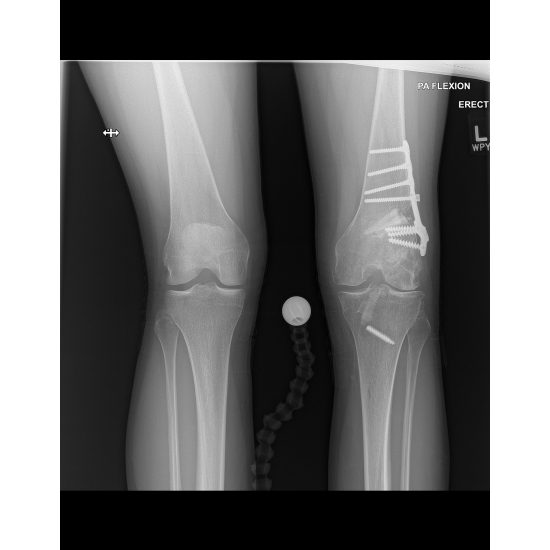

| Knee Pain 10 Years After An Acl Tear - Page #3 | |||